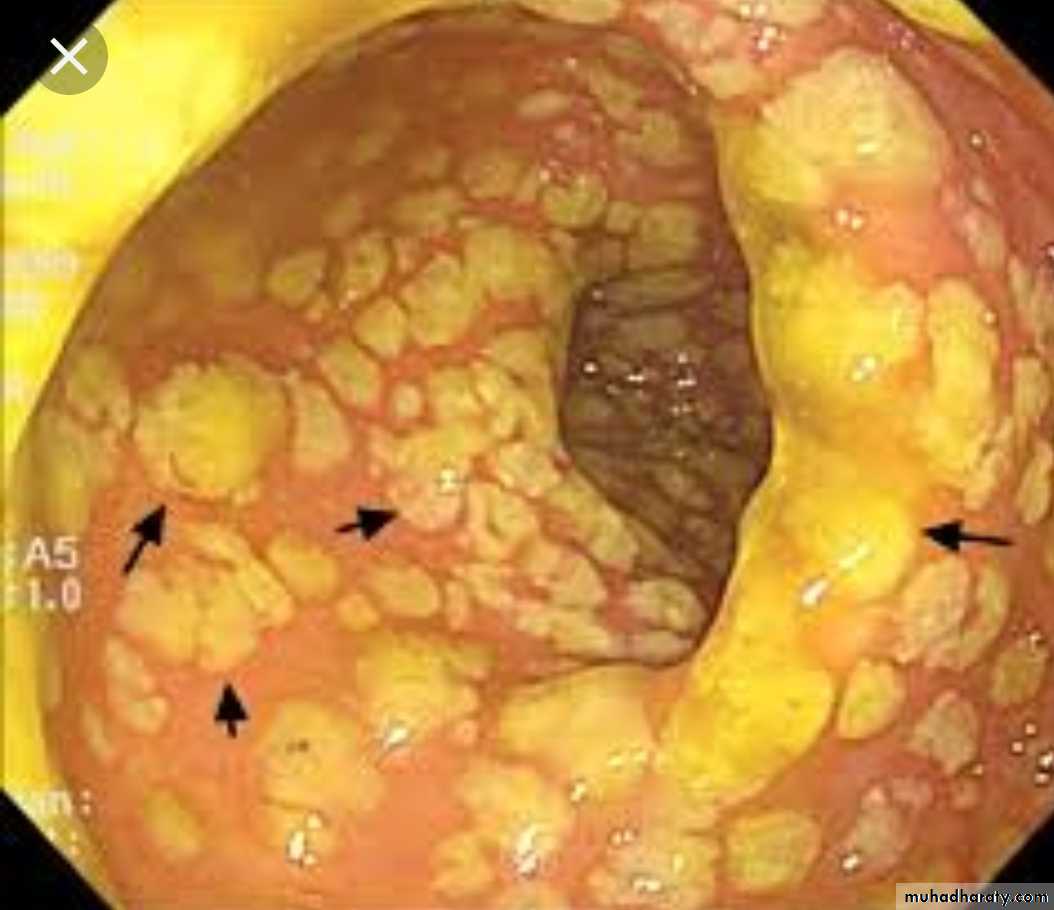

Acute Bacterial InfectionMorphological paterrns1-Catarrhal: affect mucus membrane.

Acute cattarhal gastritis